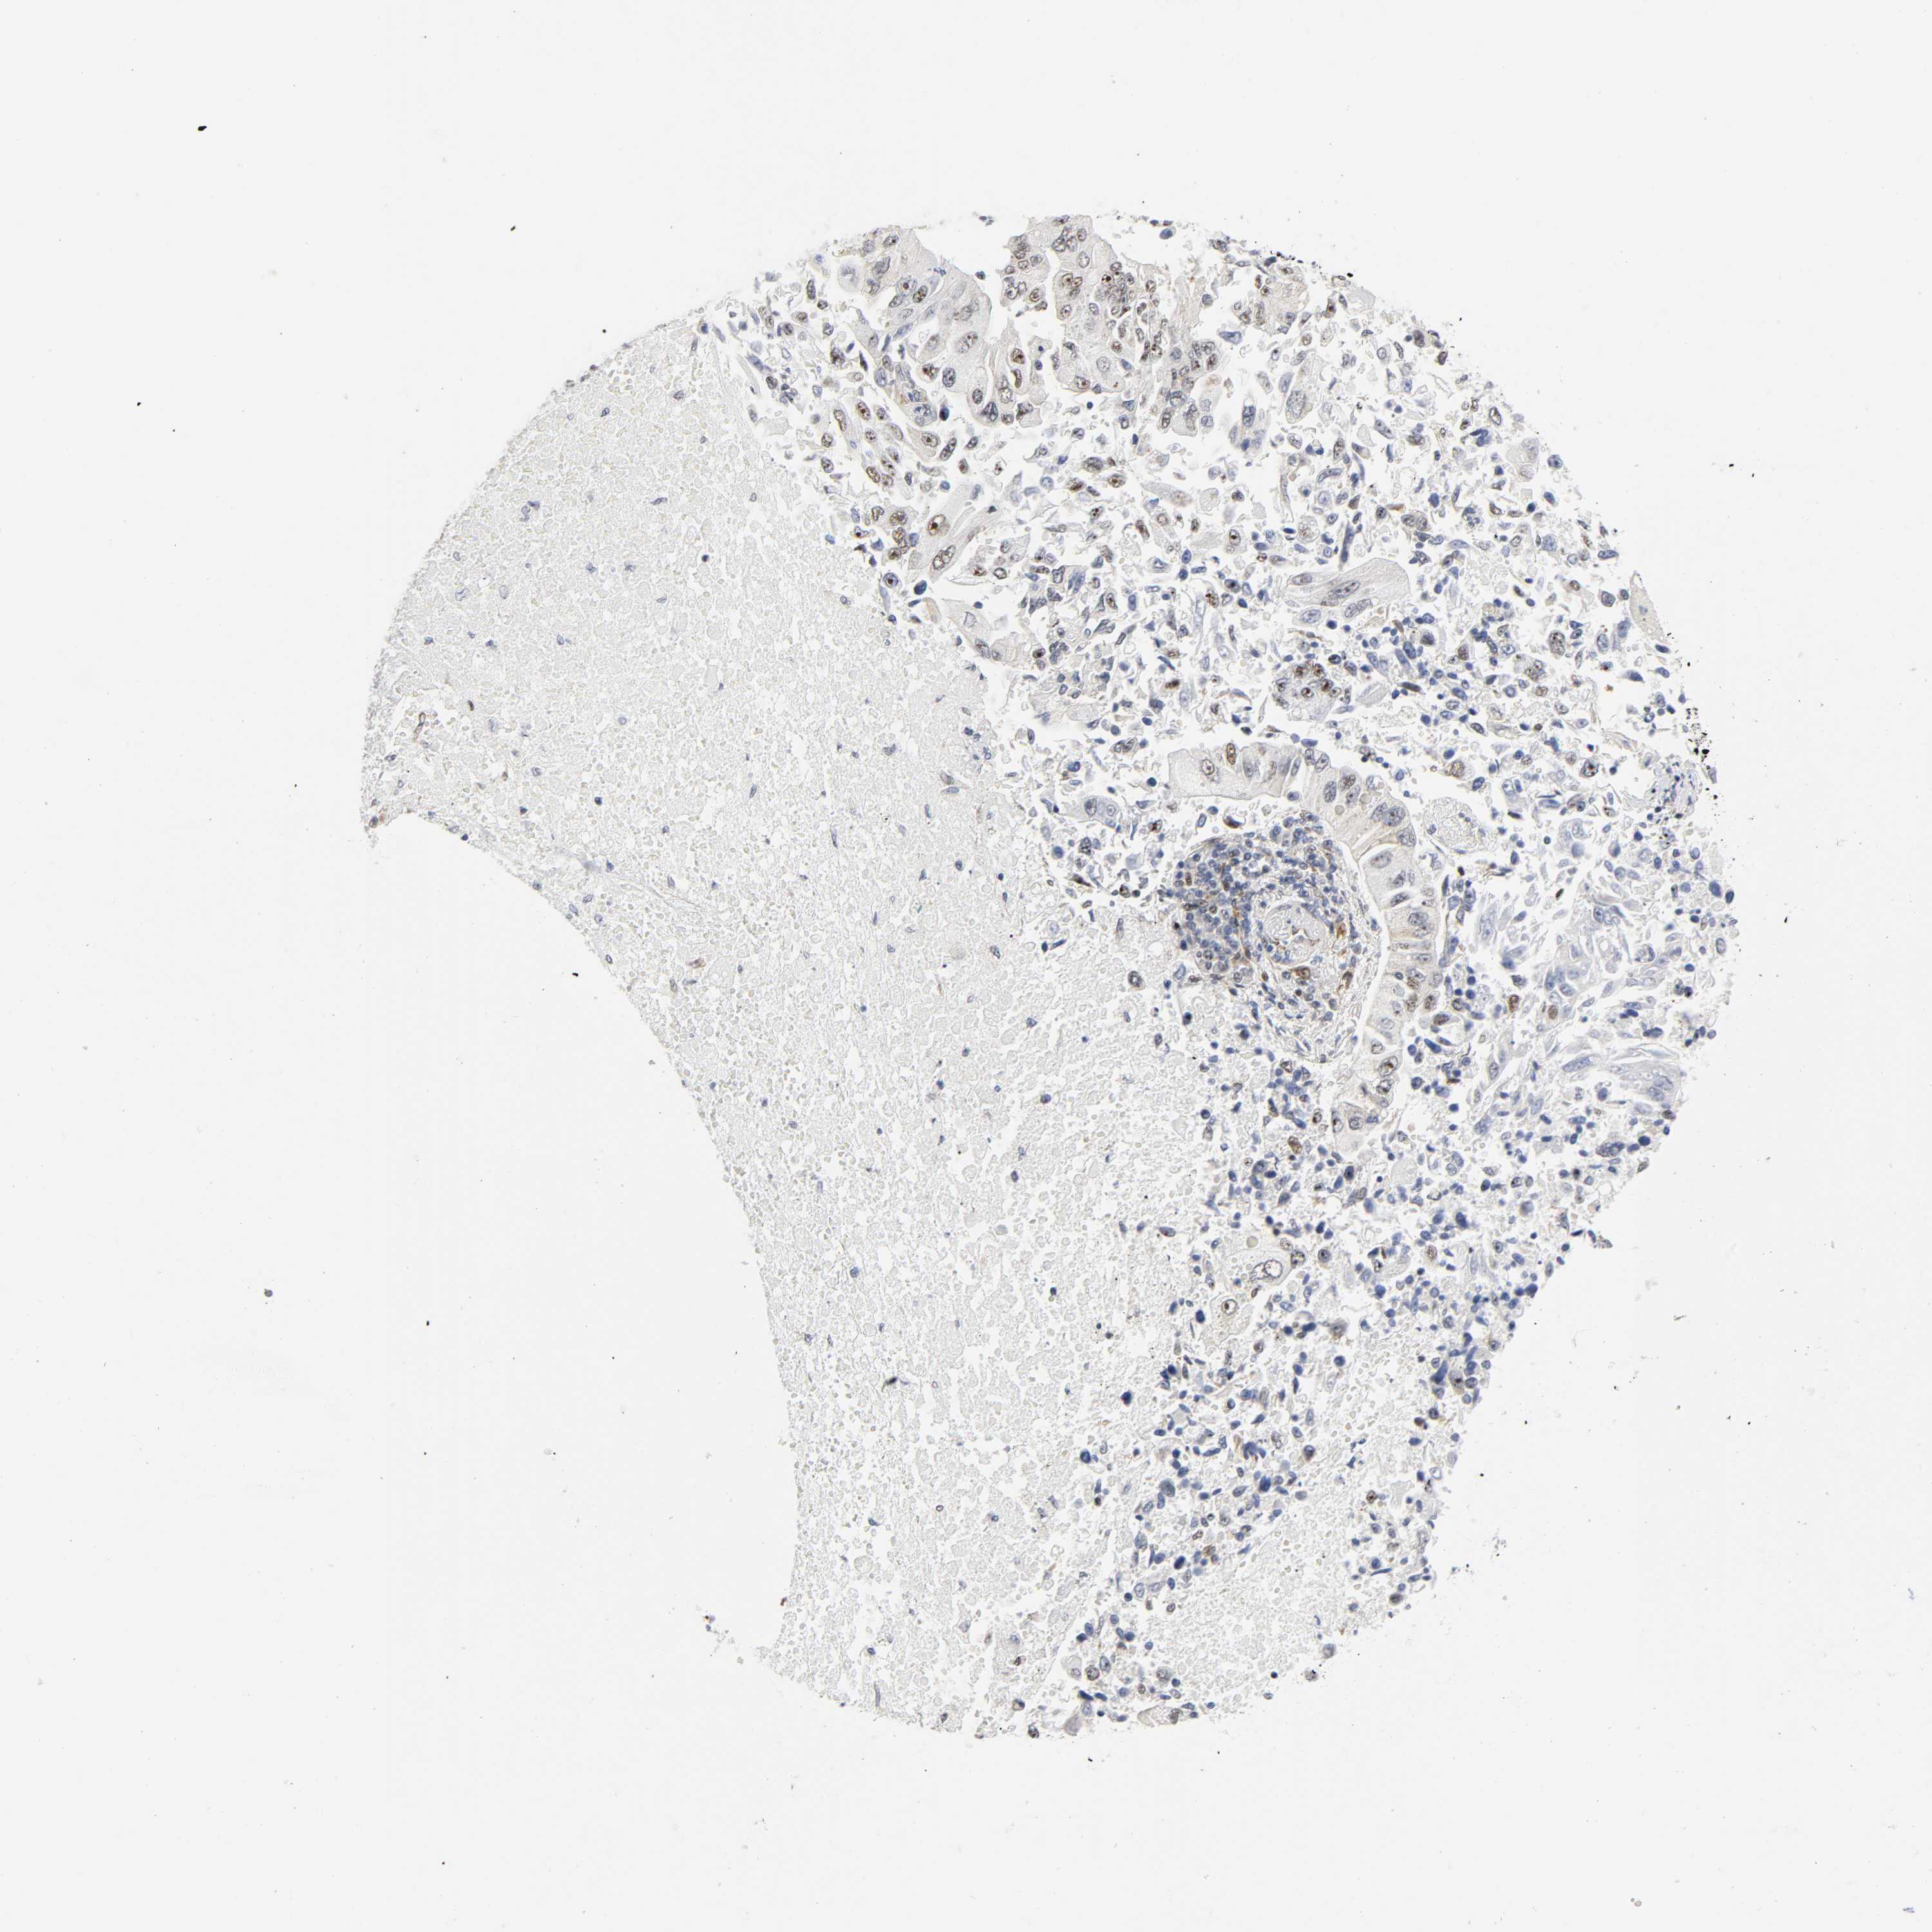

CANCER LUNG CANCER Show tissue menu

LUAD TCGA LUAD VALIDATION LUSC TCGA LUSC VALIDATION PROTEIN LUAD CPTAC PROTEIN LUSC CPTAC PROTEIN EXPRESSION